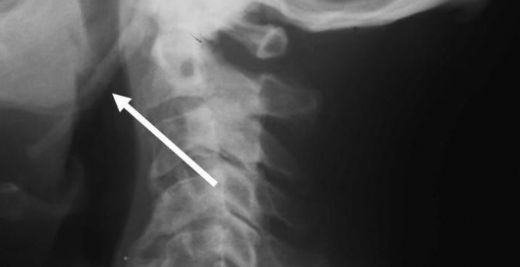

Tanı Süreci Eagle sendromunun tanısı genellikle klinik muayene ile başlar. Doktor, hastanın semptomlarını değerlendirir ve fiziksel muayene yapar. Tanıyı kesinleştirmek için görüntüleme tekniklerinden faydalanılır:

Eagle Sendromu, styloideus processusun anormal uzamasıyla ortaya çıkan nadir bir durumdur. Belirtileri arasında baş ve boyun ağrıları, yutma zorluğu ve çiğneme rahatsızlığı bulunur. Tanı süreci fiziksel muayene ve görüntüleme yöntemleriyle yapılırken, tedavi seçenekleri belirtilere göre değişiklik gösterir.

Eagle Sendromu, styloideus processusun (dil kemiği) anormal derecede uzaması veya kalsifikasyonu sonucu oluşan nadir bir durumdur. Bu sendrom, genellikle baş ağrısı, boyun ağrısı, çiğneme zorluğu ve diğer rahatsız edici belirtilerle kendini gösterir. Bu makalede, Eagle sendromunun belirtileri, tanısı ve tedavi yöntemleri üzerinde durulacaktır. Eagle Sendromunun Belirtileri Eagle sendromunun belirtileri kişiden kişiye değişiklik gösterebilir. Aşağıda en yaygın belirtiler sıralanmıştır: